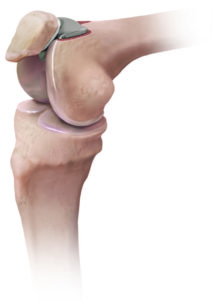

Knie

Das Kniegelenk mit seinen Pathologien stellt die Spezialität der Praxis dar. Jahrelange Erfahrung als Leitende- oder Oberärzte und grossen Spitälern ermöglichen uns Ihnen hochspezielle Operationstechniken bei allen Erkrankungen des Gelenkes anzubieten. Wir greifen hier auf die Erfahrung aufgrund eine hohe Anzahl an durchgeführten Operationen zurück welche regelmässig analysiert und von uns weiterentwickelt werden. Unsere speziellen Leistungen sind folgend aufgeführt:

Die gelenkbildenden Oberflächen des Kniegelenkes sind mit Knorpel überzogen. Dieser ermöglicht es, eine glatte, reibungsfreie Oberfläche zu bilden. Im Laufe des Lebens kommt es zu Abnutzungen dieser Knorpelflächen. Die Ursachen einer Arthrose sind sehr vielfältig und oft von verschiedenen Faktoren beeinflusst. Hohes Alter, Unfälle, Änderungen der Beinachse aber auch Übergewicht und Bewegungsmangel können die Biomechanik verändern und den Knorpel im Gelenk verschleißen. Ist der Knorpel einmal zerstört, kann er sich nicht mehr regenerieren. Der Gelenkspalt nimmt an Höhe ab bis im Endstadium nur noch Knochen auf Knochen reibt. Die Arthrose geht mit verschiedenen Symptomen einher. Der Belastungs- oder auch Anlaufschmerz, v.a. nach Ruhephasen, steht hier im Vordergrund. Hinzu können Schwellungen und Ergüsse im Kniegelenk auftreten. Bei fortschreitender Arthrose kommt es zum sogenannten Ruheschmerz, d.h. Schmerzen im betroffenen Gelenk bei absoluter Ruhe, z.B. nachts im Bett. Im Laufe der Zeit ist der Bewegungsumfang zunehmend eingeschränkt, welcher durch Schonhaltung, aber auch durch Umbauveränderungen im Gelenk, hervorgerufen wird. Je nach Stadium der Arthrose können verschiedene Verfahren angewendet werden, um möglichst bald eine Schmerzfreiheit und eine verbesserte Beweglichkeit zu erreichen.

Operative Therapie: Komplette Endoprothese des Kniegelenkes

Eine fortgeschrittene Arthrose, welche alle Anteile des Kniegelenkes betrifft, kann nur noch durch den Ersatz der kompletten Oberfläche therapiert werden. Somit können auch entstandene Achsfehler und Beinlängendifferenzen ausgeglichen, Knochendefekte aufgefüllt und die Funktion dauerhaft geschädigter Bänder ersetzt werden. Hierbei sollte darauf geachtet werden, für jeden Patienten das individuell benötigte System einer Totalendoprothese herauszufinden. So gibt es nicht nur Unterschiede zwischen Mann und Frau sondern auch in der Bandstabilität und in der bereits angesprochenen Beinachse. Somit kann gewährleistet werden, dass bei jeder Operation die bestehende Anatomie respektiert und eine optimale Funktion wiederhergestellt wird. Die von uns verwendeten Prothesenteile sind hochmodern beschichtete, bestehen aus Edelmetallen und ermöglichen ein hohes Mass an Beugefähigkeit des Gelenkes. Als Meniskusersatz benutzen wir einen hochvernetzen Kunststoff welcher als zusätzlichen Schutz noch mit Vitamin E angereichert ist.